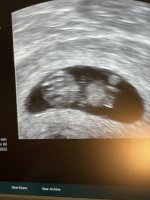

Åh så deilig! Godt å høre! ♡ liten bamsemums der jo!Lille frøet ble idag målt til 21,4 mm og tilsvarte 9+0så er altså blitt satt frem igjen i forhold til de andre TUL jeg har vært på og dette stemmer mye bedre med min beregning

Fin hjerteaksjon, og frøet hadde både armer og bein som den til og med rørte litt på

Lille frøet ble idag målt til 21,4 mm og tilsvarte 9+0så er altså blitt satt frem igjen i forhold til de andre TUL jeg har vært på og dette stemmer mye bedre med min beregning